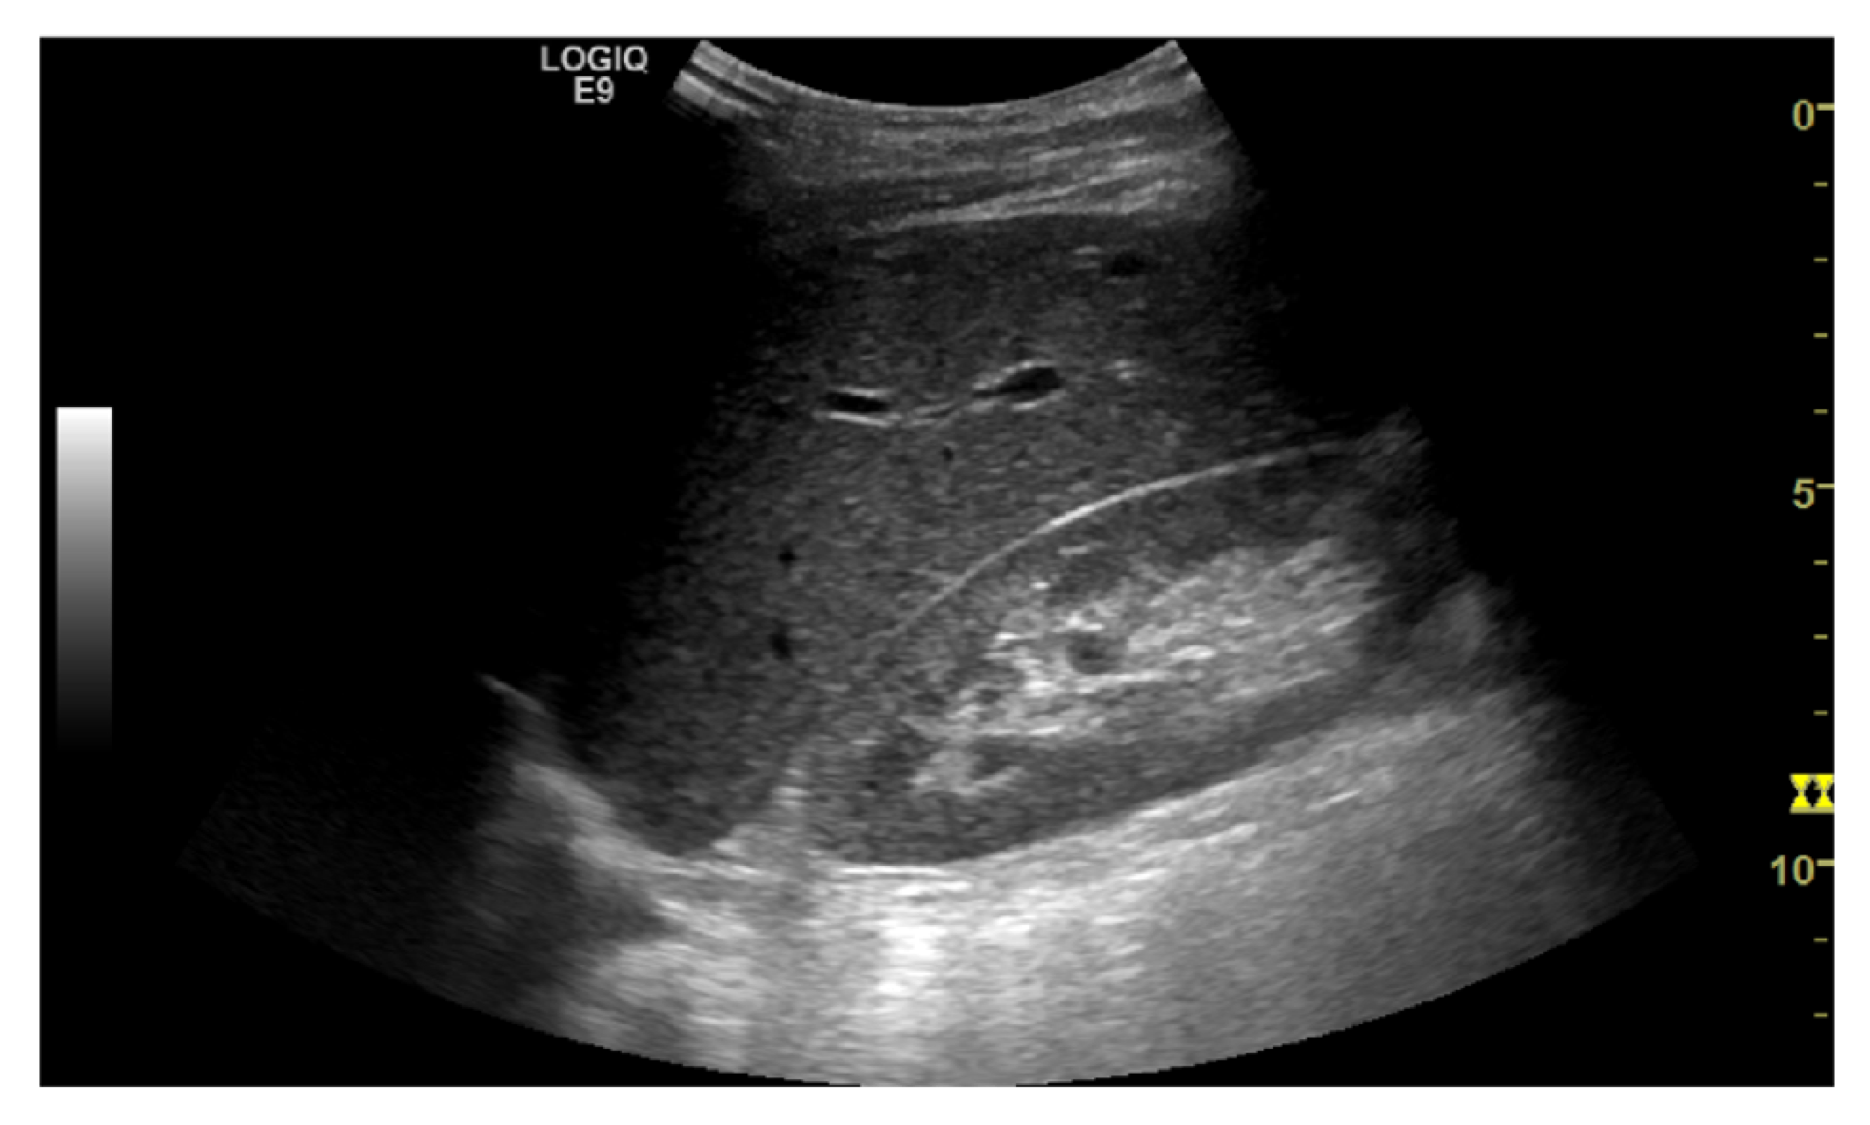

The task is to identify an optimal view for Morrison’s pouch - an anatomic site between the right lobe of the liver and the right kidney. Clinically, the view is important to identify ascites and hemoperitoneum when abnormal fluid accumulation is presented; also, it is the reference view to estimate the severity of steatosis using the hepatorenal index. Therefore, quantifying the view quality is crucial in an ultrasound examination. The images were reviewed by a board-certified radiologist and gave five different rankings as the quality measurement (Figure 4). Class 0 indicates the view does not include the liver or the kidney, and should not be used; while class 4 represent an optimal Morrison’s pouch view that will be used by an experienced operator. We used the ordinal encoding for the labels. (class 0: [0,0,0,0], class 1: [1,0,0,0], class 2: [1,1,0,0], class 3: [1,1,1,0], class 4: [1,1,1,1])

Refer to caption

(e) class 4

Figure 4: Example of quality score